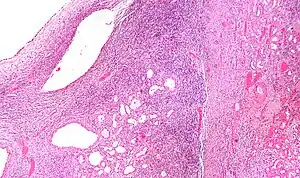

Cystic nephroma: Microscopic appearance.

High magnification micrograph of a cystic nephroma showing the characteristic simple epithelium with hobnail morphology, and the ovarian-like stroma. H&E stain.

Micrograph of a cystic nephroma. H&E stain.

The characteristics of cystic nephromas are:

- Cysts lined by a simple epithelium with a hobnail morphology, i.e. the nuclei of the cyst lining epithelium bulges into the lumen of the cysts,

- Ovarian-like stroma that has a:

- Spindle cell morphology, and has a

- Basophilic cytoplasm.